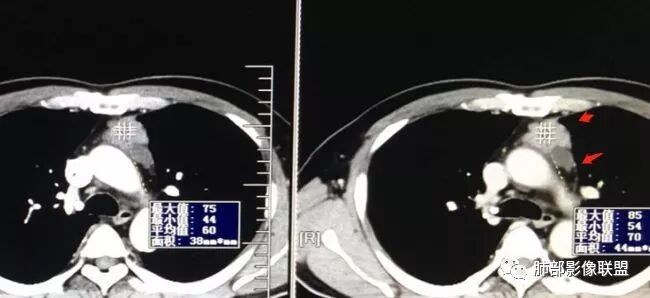

2015年小,2019年增强,不规则强化不均匀。

48-60-70,28-30-24,不规则渐进性强化,密度不均。

根据强化,高的70HU,低的没测,考虑囊实性

实性部分明显强

上面来的血供,病灶深分叶

附近心包似乎也不干净

有淋巴结